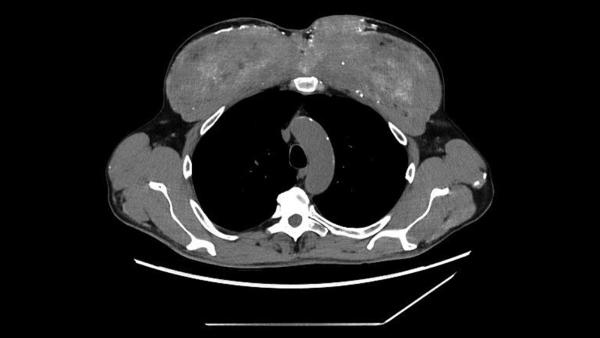

Підрозділ когнітивних та нейронних наук Кембриджського центру MRC порівняв мозок 3802 людей віком від нуля до 90 років за допомогою дифузійного МРТ-сканування. На основі цього вони визначили чотири ключові «поворотні моменти» між народженням і смертю, коли наш мозок «переналаштовується».